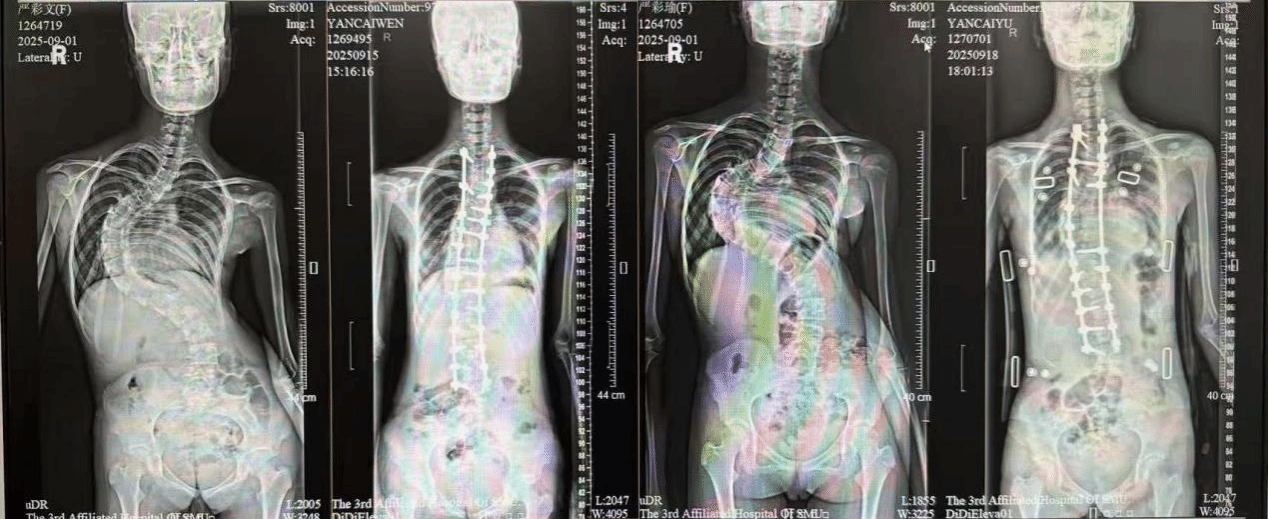

经过细致检查,王亮发现,这对双胞胎不仅外貌极为相似,连脊柱侧弯的弯型也几乎一致——两人的主弯Cobb角均超过110度,其中妹妹因先前处理不当,侧弯角度达到115度,均属于重度青少年特发性脊柱侧弯,手术难度很高。在普通人群中,青少年特发性脊柱侧弯发病率约为1%–3%,而像这样同卵双胞胎出现弯型如此相似的案例,实属罕见。

图/左1为双胞胎姐姐,左3为双胞胎妹妹

经过充分的术前准备,团队依次为姐妹俩实施了脊柱侧弯矫正手术。手术过程顺利,术后复查显示,姐姐的Cobb角由110度改善至25度,妹妹的Cobb角由115度改善至35度,躯干偏移和双肩不平衡问题均得到明显改善。更让姐妹俩欣喜的是,术后两人身高都增加了5厘米,整个人的体态与精神面貌焕然一新。